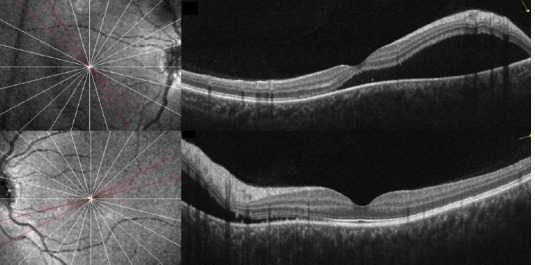

Results: A 14-year-old girl with no significant medical history reported several weeks of blurred vision in both eyes. She had been using 2% topical minoxidil on her eyebrows and eyelashes without a prescription for the past 6 months. The initial examination revealed that the best-corrected visual acuity (BCVA) was 20/80 in the right eye and 20/25 in the left eye, with no abnormalities noted in the anterior segment. Fundus evaluation and OCT confirmed bilateral serous retinal detachment. Given the patient's unsupervised minoxidil use, a causal link to central serous chorioretinopathy (CSC) was suspected. After discontinuing the drug, the subretinal fluid (SRF) resolved, and visual acuity fully recovered within three months, supporting the association between minoxidil and choroidal neovascularization (CNV), not CSC.